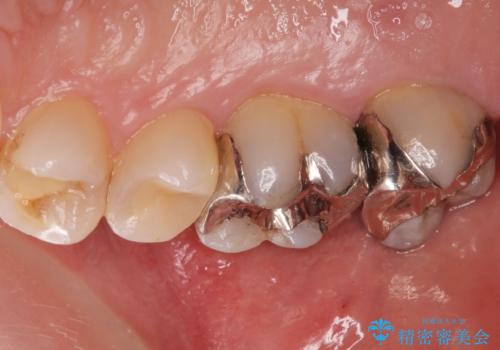

奥歯がしみて痛い

- 冷たいものがしみて飲み物が飲めないとの事で来院。

歯肉が退縮していたので歯周外科手術(歯茎の移植手術)か被せ物で覆う(歯肉退縮しているところまで覆う)の提案をしたところ被せ物がいいとのことでしたので

被せ物の治療のご案内になりました。

適合の良い被せ物が入りました。

冷たいものがしみなくなり大変満足してもらいました。

一つ前の歯も後に染みてくる可能性があるとの事で被せ物をするか検討中です。